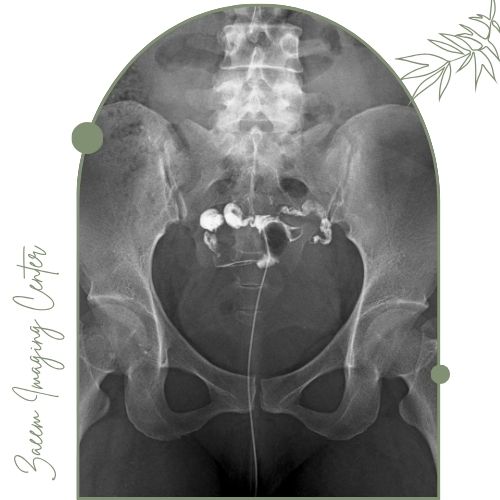

هیستروسالپنگوگرافی (Hysterosalpingography - HSG) یک روش تصویربرداری تخصصی است که برای ارزیابی وضعیت رحم و لوله‌های رحمی (فالوپ) بانوان انجام می‌شود. این تست با تزریق ماده حاجب (رنگ مخصوص) و تصویربرداری با دستگاه اشعه ایکس امکان بررسی ساختار، فرم و باز بودن مسیر لوله‌های رحم را فراهم می‌آورد.

انجام تست: بیمار به پشت روی تخت دراز می‌کشد. اسپکولوم وارد واژن می‌شود و ناحیه گردن رحم تمیز و ضدعفونی می‌گردد. با ابزار مخصوص ماده حاجب به آرامی داخل حفره رحم و لوله‌های رحمی تزریق می‌شود. پس از تزریق تصویربرداری با اشعه ایکس انجام می‌گیرد و تصاویر زنده یا سریالی ثبت می‌شود.

پایان تست: تزریق رنگ معمولاً چند دقیقه طول می‌کشد. تصاویر توسط رادیولوژیست تفسیر و برای پزشک مربوطه ارسال می‌شود.